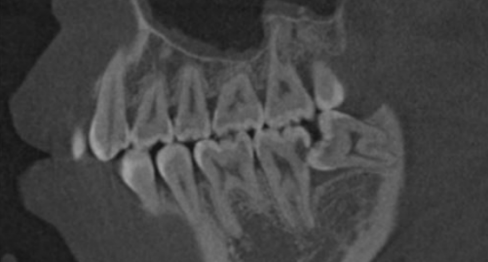

看牙为什么要拍CT?

先放几张图,让你涨涨姿势,

不拍CT根本不知道你的牙齿长得会有多奇葩!